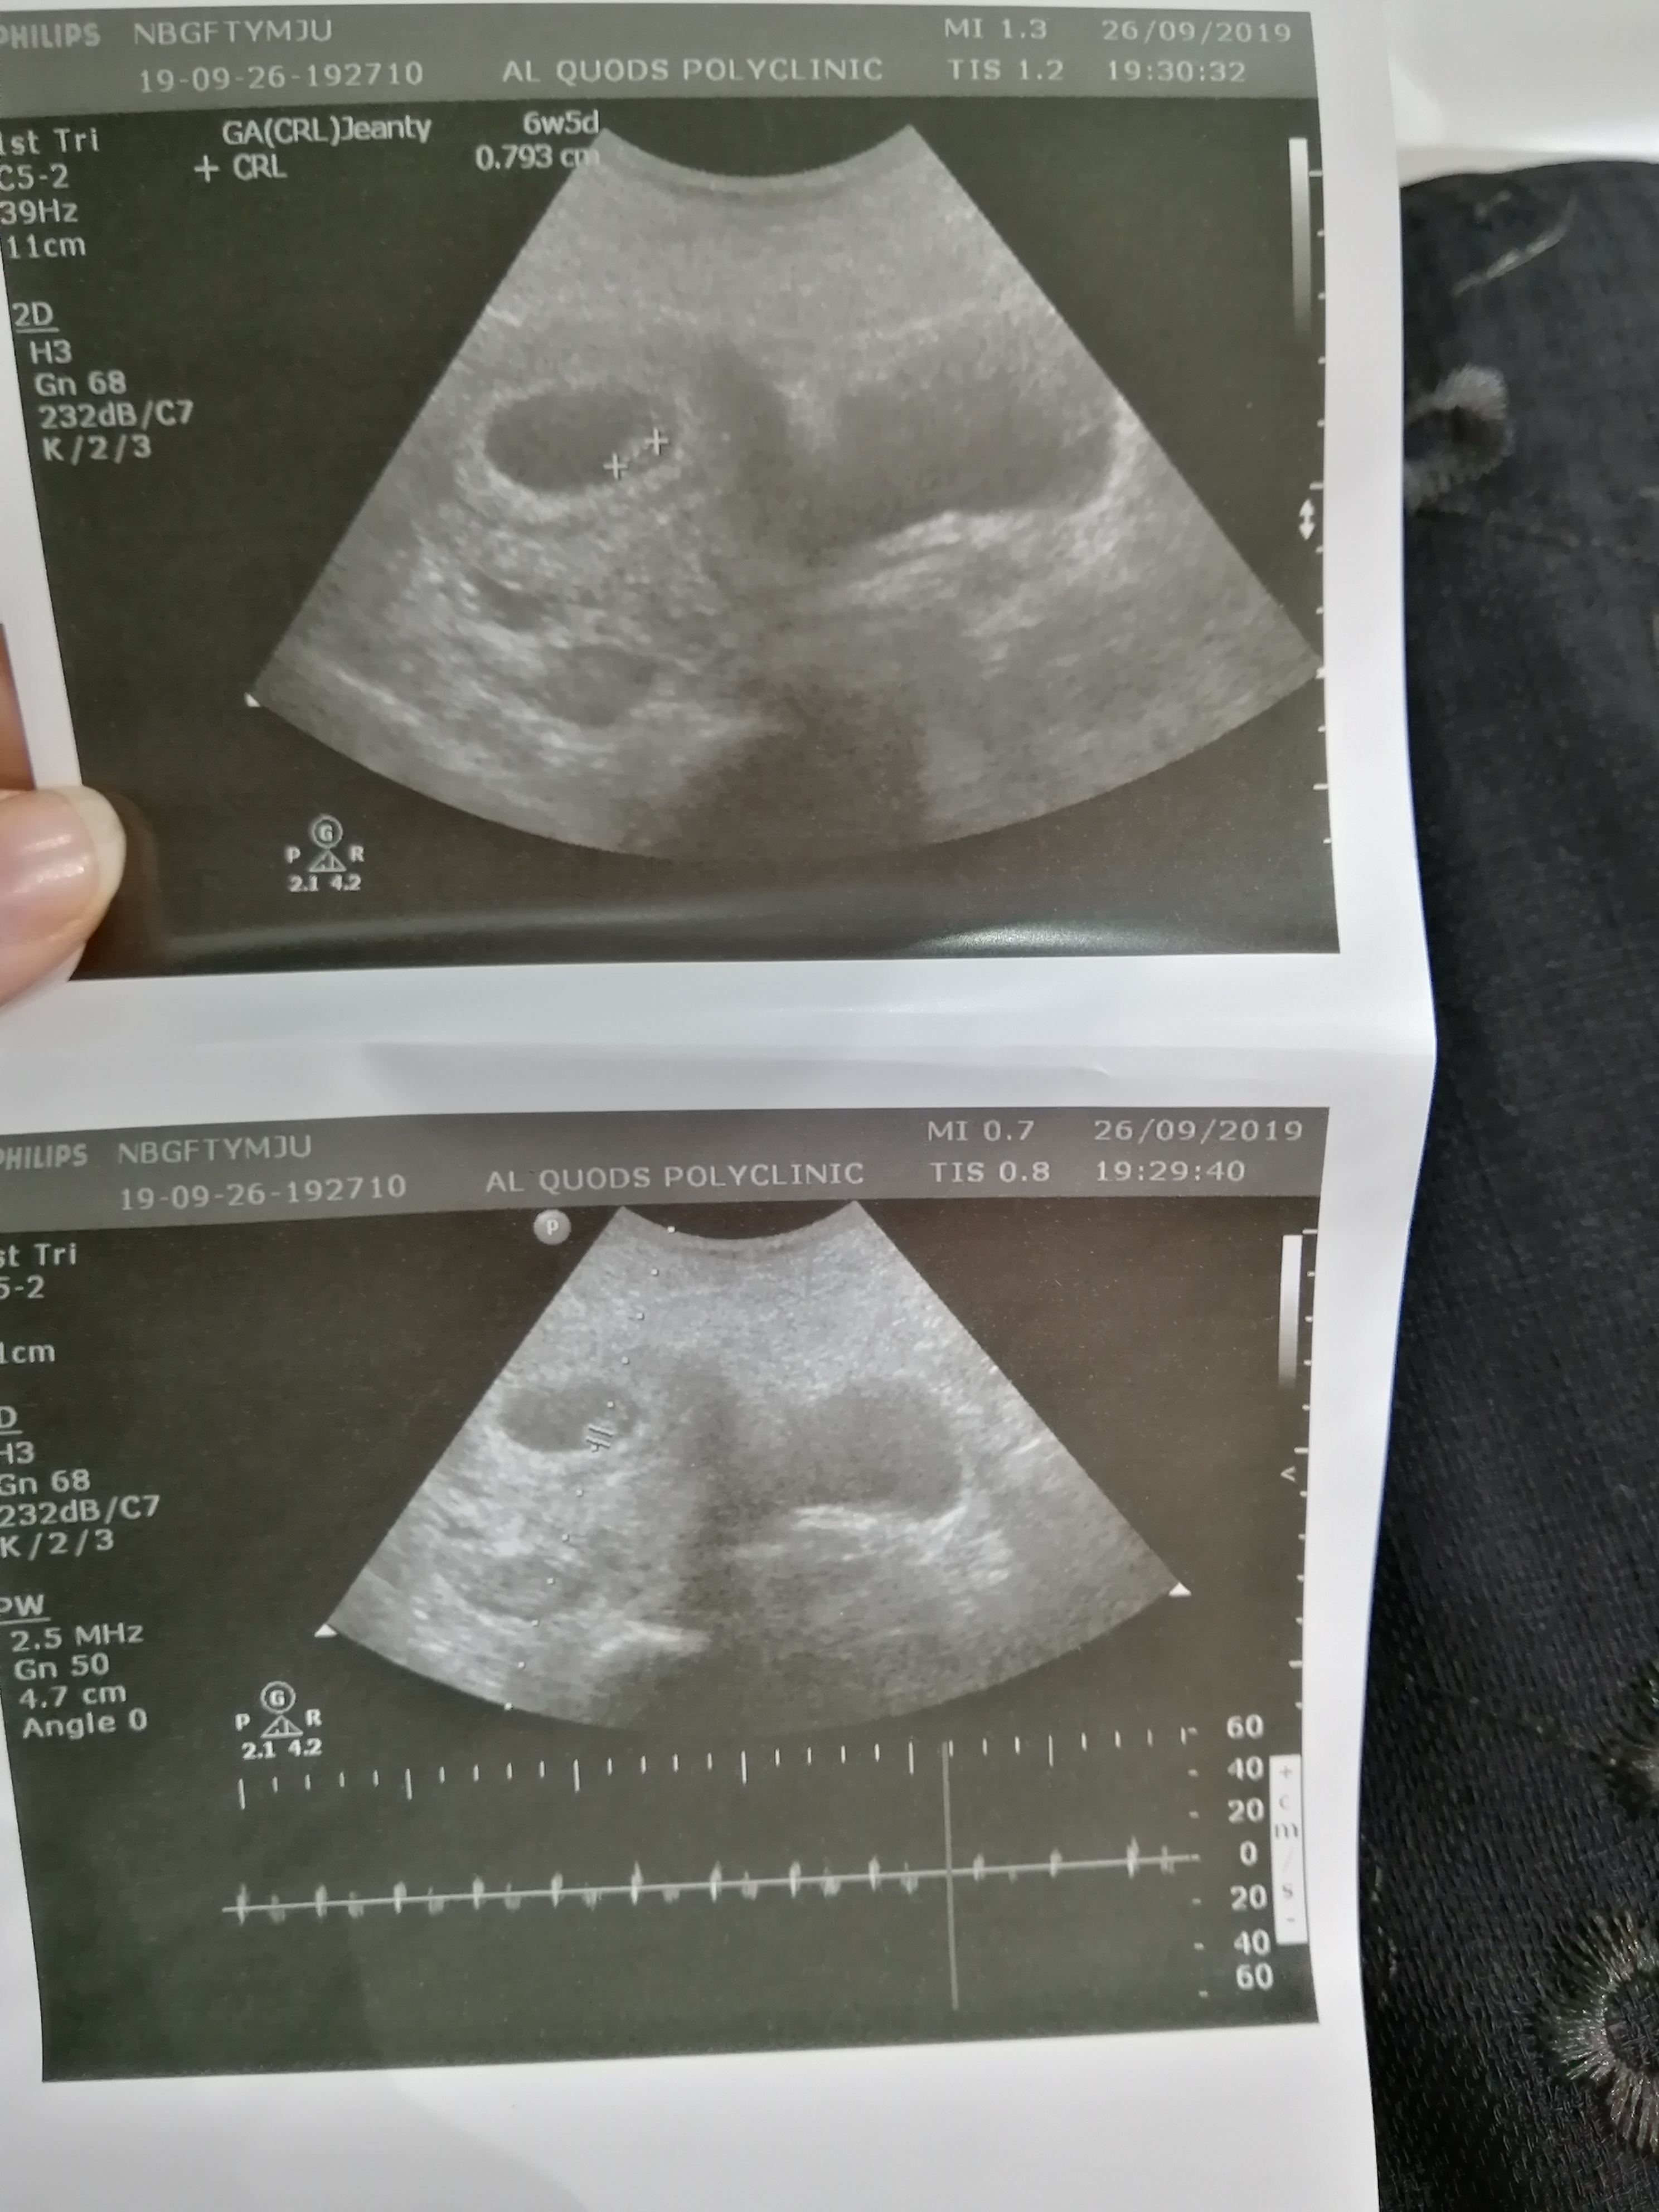

I have been reading up on the ramzi theory and wondered what you all thought of my abdominal scan taken at 6 weeks?:think:

I think Ramzi does work, but you need to know were placenta is located and therefor you can not just guess from a photo, since you can not see were placenta is from a pic. Sonographers can flip the image for instance. So don’t believe in it too much. From just a photo it can be both boy or girl.